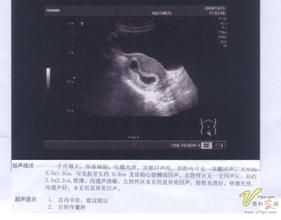

在胚胎髮育的早期胚芽時就可通過B超看到心管搏動,最早可以在6-8周(自停經時算起),如果10周還未檢測到心管搏動,在排除了末次月經可能記錯了日期的情況下可以診斷胚胎停止發育,就像自然界中所有的物種存在的優勝劣汰一樣,可能是本身種子質量問題無法發育成功。

聽胎心是醫生用聽診器所聽到的胎兒心率,而胎心博動主要是孕早期,通過B超觀察到的胚胎心臟博動. 一般12周左右可以觀察到胎心搏動,如果B超檢測未見胎心博動,即寶寶已經停育,需要流產清宮。 一般早期能見到卵黃囊,提示胚胎正常的,胎心搏動要等胚芽出現了才能看到的。孕囊一般在孕5周左右可見。而胚芽,6~7周才可見。

C)B超觀察:這種方法一般是針對有特殊狀況的準媽媽,而且只能在醫院進行。